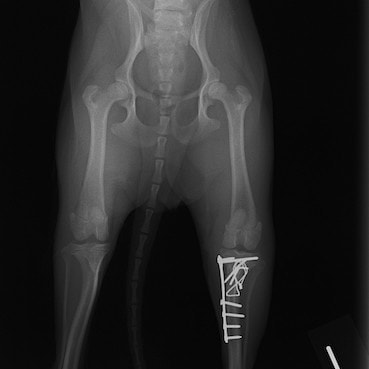

脛骨骨折 : 症例1 | 症例2 | 症例3 | 症例4 | 症例5

症例3:キルシュナーワイヤーのピンニングによる整復

ペルシャ猫 11ヶ月齢 雄

他院にて左大腿骨遠位の成長板骨折(salter-harrisⅠ型)が認められており、治療相談を目的として来院。当院にて、キルシュナーワイヤーを用いたピンニングにより骨折部位の整復を行いました。術後の経過は良好で、現在も経過観察中です。

術前レントゲン

術後レントゲン